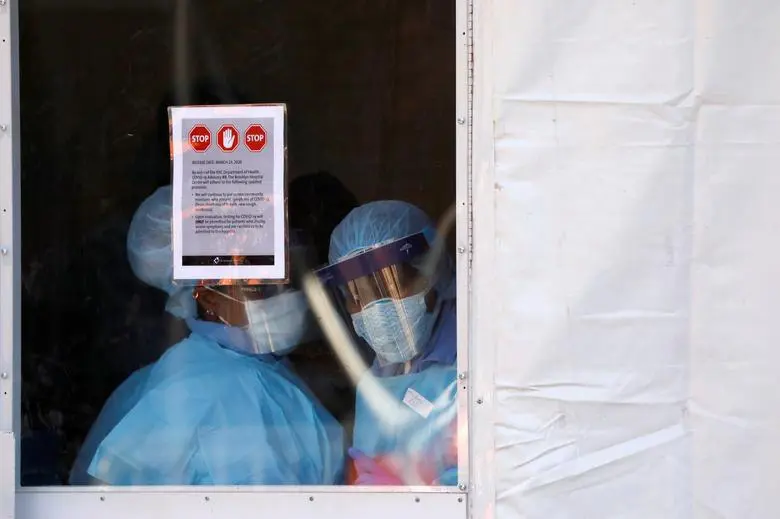

ئەم پزیشک و پڕۆفیسۆرەی زانکۆی گشتی لێکۆڵینەوە پزیسکییەکانی پیرۆگۆف ڕایگەیاند : ڤیرووسی کۆرۆنای نوێ ، جۆرێک نەخۆشییە کە کارکردنی سیستەمی هەناسەدانی مرۆڤەکان تووسی کێشە دەکات و دەبێتە هۆکاری گەیاندنی زیانی زۆر بە سییەکان .لە سەرتاسەری جیهان ، زیاتر لە ٧.٥ میلیۆن کەس لە ئێستادا تووشی ئەم ڤیرووسە بوونە ، لەم ژمارەیە زیاتر لە ٣ میلیۆن کەس چاکبوونەتەوە . هەروەها لە ڕووسیا نزیکەی ٢٥٠ هەزار کەس چاکبوونەتەوە و هەندێکیش لەوانە کێشەی زۆی جیددی یان هەیە .

ئە لێردەدا جەختی کردەوە کە : لە دوای هەوکردن بە هۆی ڤیرووسی کۆرۆناوە لە سییەکاندا گۆڕانکاری فیرۆز وەکوو باقی نەخۆشییە هەوکەرەکاندا دەبینرێت . ڕەواڵی چاکبوونەوە دوای ڤیرووسی کۆرۆنا هاوشێوەی ئەوەی کە لە ئەنفڵۆنزای بەراز کە لە ساڵی ٢٠٠٩ دا گشتگیری جیهانی هەبوو لە بەرچاو گیراوە .

هەروەها ووتی : ژیمناستیکی هەناسەدان و هەروەها ڕژیمێکی بەهێزکەر هیچ بەربەستێکی نییە و دەتوانن ئەنجامی بدەن ، بەڵام هەموو ئەمانە پەیوەندی بە توانایی تاکەکەسی هەر کەسێکەوە هەیە کە بە ڤیرووسی کۆرۆنا تووش بووە بۆ سەرلە نوێ چاککردنەوەی بنچینەی لەشی زیان پێکەوتوو وابەستە دەبێت